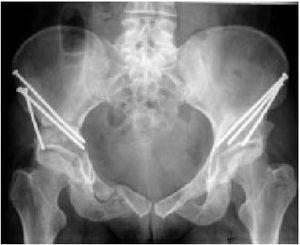

Figura 21 Tras la fijación debe comprobarse de nuevo con escopia con movilización simultánea de la cadera, para descartar la entrada de tornillos en la cadera. La cabeza femoral debe tener libre movilidad en todas las direcciones. La radiografía muestra una paciente nacida en 1962 tras osteotomías bilaterales. El lado izquierdo se operó en 1998 y el derecho en el año 2000. Cierre cuidadoso de la herida. Se fijan los músculos liberados a la espina ilíaca anterosuperior y a la espina ilíaca anteroinferior con sutura transósea. Se reconstruye el conducto inguinal con mucho cuidado. Se deja un drenaje de aspiración. Tratamiento postoperatorio

* Se realiza una radiografía postoperatoria (fig. 21) durante la estancia en el hospital. El paciente puede ser dado de alta generalmente después de 7-10 días. El apoyo parcial del peso se continúa por 8-10 semanas. Las visitas de control del paciente ambulatorio con una exploración clínica y las radiografías se hacen en 6-8 semanas y entonces en 6 y 12 meses El retorno a la actividad completa es posible generalmente después de 4-6 meses. La fisioterapia adicional es escasamente necesaria.